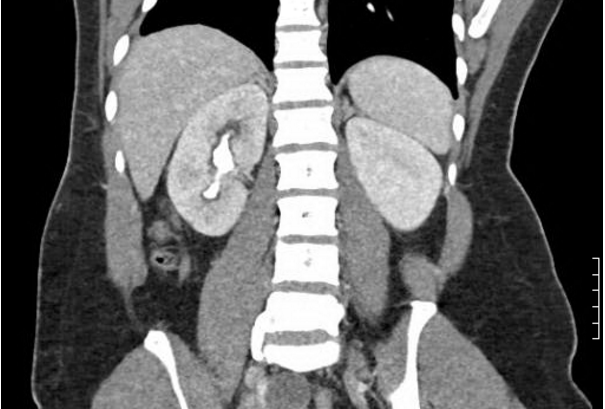

Pathophysiology and Treatment of Infection Stones

- Pathophysiology of infection stone formation

- Workup of patients suspected of having infection stones, including imaging

- Surgical management